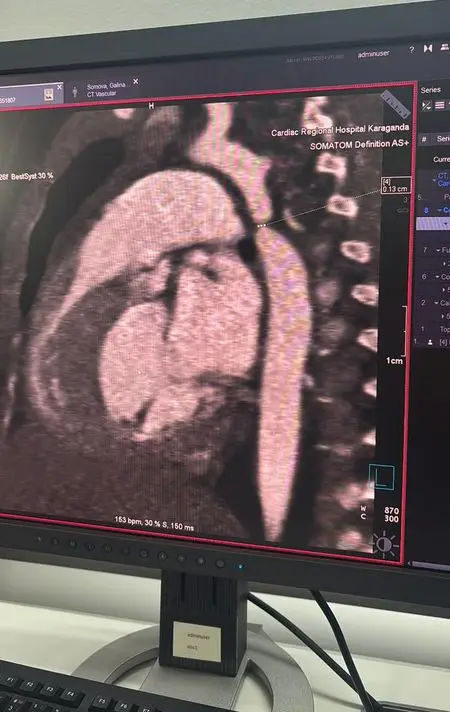

В Караганде в многопрофильной больнице №2 (Кардиоцентр) успешно завершилась сложная операция на сердце для трёхмесячной девочки, у которой была диагностирована критическая коарктация аорты. Первоначально ребёнка госпитализировали с пневмонией в многопрофильную больницу №1, где во время обследования врачи обнаружили опасное заболевание, требующее немедленного вмешательства.

Операция длилась почти пять часов и включала резекцию коарктации аорты с наложением анастомоза "конец в конец", что позволило полностью восстановить кровоток. В ходе вмешательства также была выявлена открытая артериальная протока, которую успешно легировали. По словам Галымжана Утегенова, операция была технически сложной, но прошла в плановом режиме.